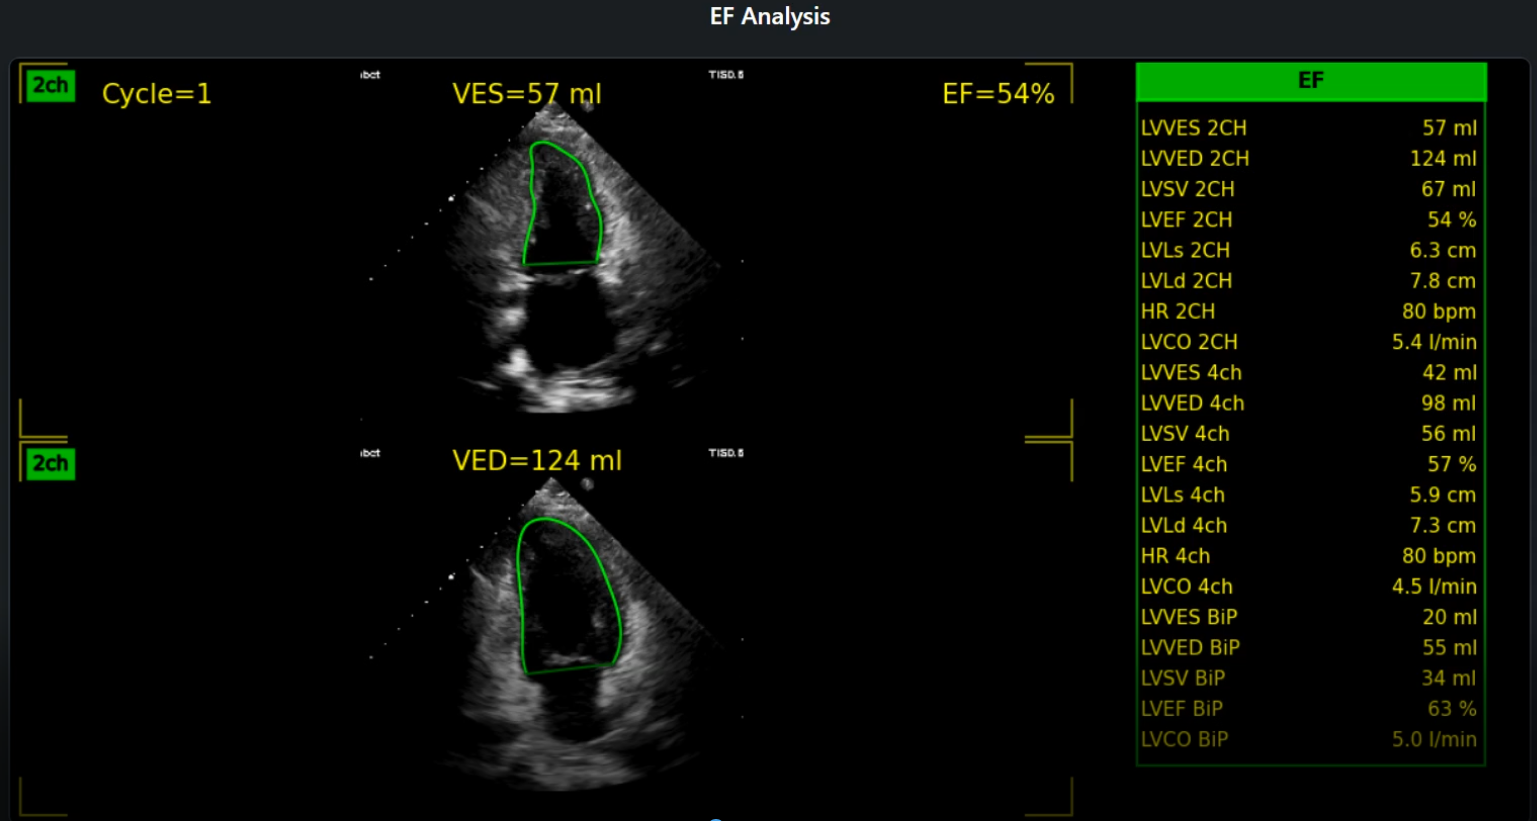

• Automated LV Volume & EF: Precisely calculate Left Ventricular (LV) end-diastolic and end-systolic volumes, and Ejection Fraction (EF) using advanced AI algorithms.